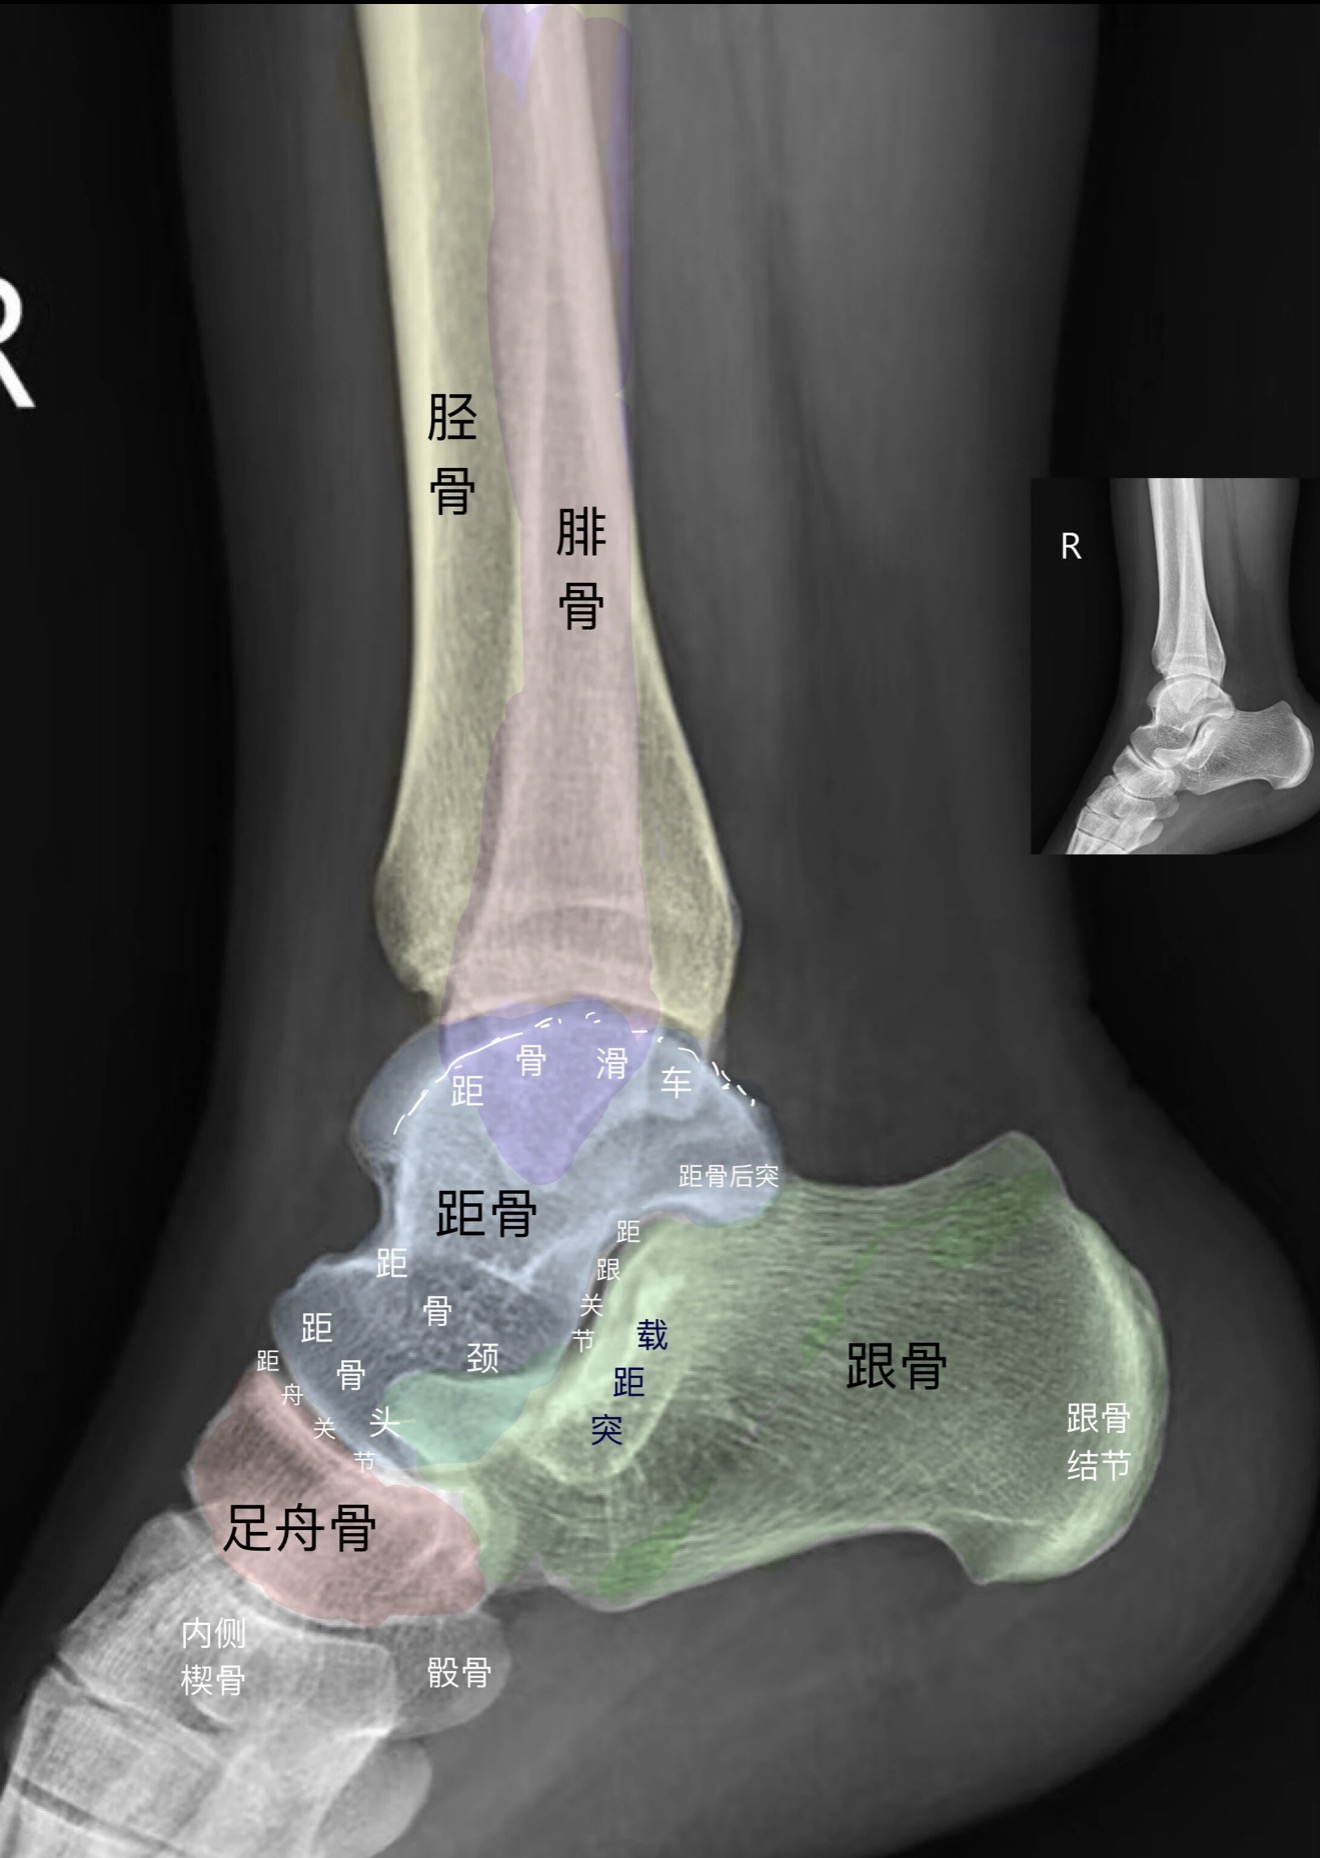

分享DR踝关节正侧位影像图 #医学影像科普#踝关节DR影像解析#DR踝关节解剖